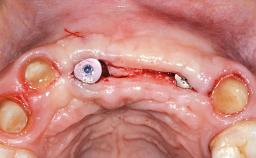

A 45-year-old woman was referred for management of an infection associated with two implant-supported crowns replacing the maxillary central incisors. Two tissue-level implants had been placed and restored with cemented single metal-ceramic crowns in those sites 4 years previously. The patient presented with a draining sinus (i.e. a pathological duct from an abscess cavity to a surface) 3 mm from the midfacial peri-implant mucosal margin of the maxillary right implant crown. She was in good general health, did not smoke, showed a good oral hygiene status, and had no history of periodontal disease. The implants were well positioned. While the patient was very satisfied with the appearance of her crowns, she had noted that the peri-implant soft tissue had receded since their insertion and was concerned about the possibility of further recession.